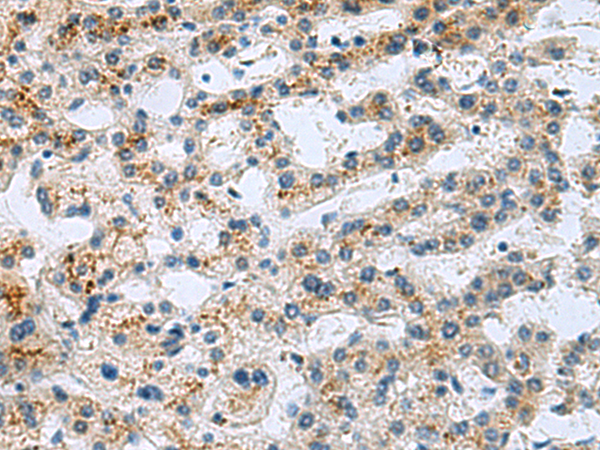

分类: 科研抗体货号: P06324别名: GRFR; GHRFR; IGHD1B应用: IHC反应种属: Human